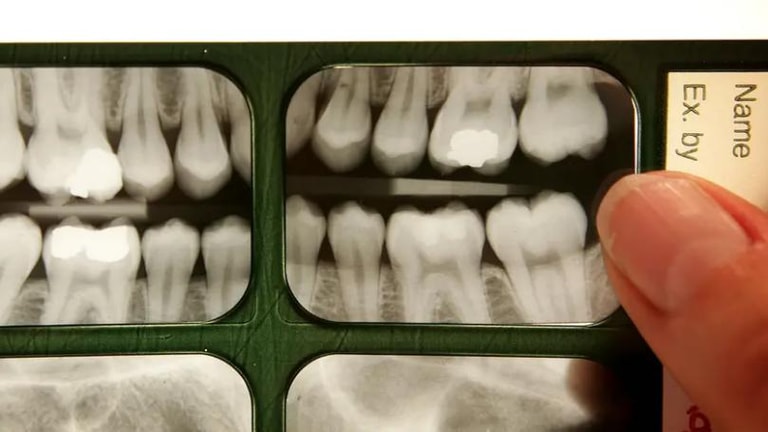

Slow body development over the course of life, as well as shorter jaws and retracted faces in humans compared to those in chimpanzees could explain why molar teeth grow much later in people than in our primate cousins, finds a new study.

While chimpanzees get adult molars – the chewing teeth towards the back of the mouth – when they are around three, six and 12 years old, humans grow these at around 6, 12 and 18 years of age, extending into adulthood.

Since molars do not emerge until a point when enough facial growth has occurred, the scientists believe “the finer details of the model could be explored in more samples to help understand the phenomenon of impacted wisdom teeth in humans.”

The findings, the scientists believe, could help advance the clinical understanding of wisdom teeth.